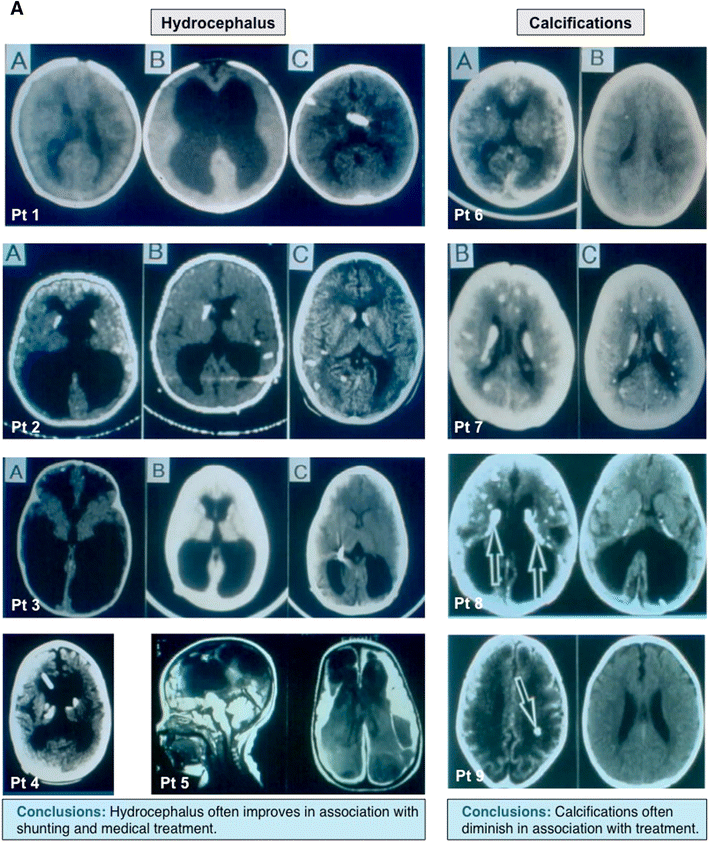

Manifestations of congenital toxoplasmosis and outcomes of treatment. a Neurologic manifestations of congenital toxoplasmosis and response to treatment. Brain CT images depicting the impact of proper shunt placement and treatment of congenital toxoplasmosis on the course of hydrocephalus secondary to T. gondii infection. Adapted with permission from McLeod et al. [207]. b Congenital toxoplasmosis, its impact on the retina, and the effect of treatment on eye lesions. Effect of treatment on the recurrence of eye lesions secondary to T. gondii infection, with increased frequency of occurrence at entrance into school and at adolescence. c Response of active eye lesions to treatment. Treatment of eye lesions leads to resolution of overlying vitritis, hazy margins and sharp demarcation and hyperpigmented lesions. d Choroidal neovascular lesions and their response to anti-T.gondii treatment and antibody to VEGF. The first image is a patient with choroidal neovascular membrane and the resultant resolution with treatment. Note the presence of blood and subretinal fluid, which decreases following treatment with appropriate therapy. Adapted with permission from Benevento, McLeod et al. [206, 207]. Additional choroidal neovascular membranes and their response to treatment in additional patients. The impact of prompt, appropriate treatment of choroidal neovascular membranes in a series of patients. Evidence of bleeding decreases, as does the presence of subretinal fluid in these patients. Adapted with permission from Benevento, McLeod et al. [206]. e Literature outcomes in congenital toxoplasmosis and outcomes in the NCCCTS cohort. A comparison of frequency of outcomes as reported by literature and within the National Collaborative Chicago-based Congenital Toxoplasmosis Study cohort. Note the dramatic decreases in the frequency of outcomes in this particular cohort relative to literature sources. This is true for many outcomes, including IQ, motor function, retinal lesions, and central nervous system manifestations. Adapted with permission from McLeod et al. [206, 207]. f The treatment of congenital toxoplasmosis, in utero, and outcomes due to this early treatment. The impact of treatment, in utero, on the frequency of disease manifestation in congenital T. gondii infection. Note the increased frequency of most disease manifestations without the initiation of treatment, in utero. Adapted with permission from and McLeod et al. [207]. g Parasite serotype and its relationship to treatment efficacy. Tabular representation of the impact of parasite type on outcomes in treated patients. Postnatal treatment was effective (i.e., improved outcomes) in both type II and type NE-II parasites, indicating that both respond to treatment. Adapted with permission from and McLeod et al. [207]. h Outcomes in NCCCTS cohort compared to the literature. Data indicating improved outcomes in treated patients over preexisting literature data on pre-established endpoints, including neurologic outcomes, reductions in IQ, worsened vision, new retinal lesions, and hearing loss. Adapted with permission from McLeod et al. [206, 207]. (I) Dosage of Pyrimethamine and its Impact on Treatment Outcomes. Kaplan–Meier plots indicating no significant differences in outcomes between two treatment arms receiving higher doses of Pyrimethamine versus lower doses. In practice, infants with less severe manifestations often receive the lower dose of Pyrimethamine, though with severe disease often are still treated with higher doses. Adapted with permission from McLeod et al. [206, 207]

This can be accomplished by recognition of clinical findings compatible with the congenital infection in the infant of an acutely infected mother (Table 1, Fig. 2). Typical clinical findings include prematurity, intrauterine growth retardation, being small for gestational age, “rule out sepsis,” blueberry muffin rash, petechiae, hepatitis, splenomegaly, hepatomegaly, anemia, leukopenia, thrombocytopenia, abnormal cerebrospinal fluid cells, protein, or glucose, IgM specific for T. gondii or cerebrospinal fluid with T. gondii-specific DNA present demonstrated by PCR, intracerebral calcifications, microcephalus, hydrocephalus, chorioretinal scars or choroiditis and vitritis, vitreal veils, uveitis, and cataracts. Diagnosis may be confirmed by isolation of T. gondii from placenta or peripheral blood buffy coat [95], demonstration of T. gondii by PCR of placenta, or serologic testing with the demonstration of T. gondii-specific IgM or IgA. These antibodies are present in only approximately 70 % of infected babies. Images depicting some of these findings, and their improvement with treatment, are shown in Figs. 2, 3, 4. In general, disease manifestations among untreated infants are more severe when infection is acquired earlier in pregnancy and less severe when acquired later in gestation, although parasite and host genetics play a major role in outcomes as well [77, 121••,122, 123••, 124, 125, 126, 127, 128, 129•, 130•, 131, 132, 133••, 134••, 135•, 136•, 137, 138, 139, 140, 141•, 142, 143, 144, 145, 146, 147]. There appear to be four primary genetic parasite types in the USA. Type 2 parasites, similar to those in Europe, also are present in the USA. There is less severe disease and risk of prematurity in those with Type 2 infection, although there is not a complete correlation between parasite type and severity of congenital infection. The inoculum size of ingested parasites, including acquisition of oocysts and contaminated meat in epidemic settings, likely also play a role in outcomes [148] Obstructive hydrocephalus due to obstruction of the Aqueduct of Sylvius results in third ventricular dilatation. This pattern of hydrocephalus may be associated with cerebrospinal fluid protein levels of >1 g/dL. Obstruction of the Foramen of Monroe can lead to unilateral or bilateral ventricular dilatation. Hydrocephalus can also occur without anatomic obstruction of CSF circulation. For example, communicating hydrocephalus, which may be due to loss of brain parenchyma, or hydrocephalus associated with poor reabsorption of cerebrospinal fluid, presumably due to a fibrotic process, can occur. This latter pathogenesis is apparently similar to that seen in normal pressure hydrocephalus in adults. All patterns of hydrocephalus can benefit from shunt placement (Hutson, McLeod, McLone, Frim, et al., in preparation 2014);the prognosis is guarded if a shunt is not placed or placement is delayed when necessary.

Approach to Cerebral Ventricular Enlargement

Delays in shunt placement have been associated with less favorable outcomes [96]. Endoscopic third ventriculocisternostomy (ETV) frequently fails as a treatment for aqueductal obstruction causing hydrocephalus in this disease [96] and should not be used [96]. A possible cause of this failure of ETV is entry of inflammatory CSF into the subarachnoid space, resulting in adhesions and inadequate CSF absorption. It is not uncommon for children to have cortical expansion and restoration of normal ventricular volume and neurologic function (Fig. 4). High CSF protein and diabetes insipidus have been linked to less favorable outcomes, but this is not absolute.